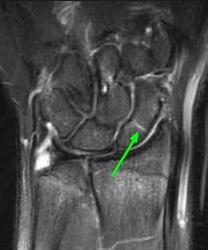

MRI

Nếu nghi ngờ về lâm sàng, MRI rất nhạy trong phát hiện gãy xương thuyền, sớm nhất là 2 ngày sau chấn thương. Lợi ích của MRI:

- xác định ngay lập tức các vết gãy/tổn thương dây chằng

- đánh giá tình trạng mạch máu của xương (mạch máu ở đầu gần)

- rất tốt để đánh giá gãy xương ẩn

MRI có độ nhạy 97.7%m và độ đặc hiệu 99.8%.